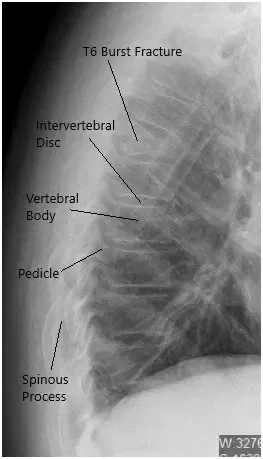

Preoperative X-ray of the Thoracolumbar Spine in Lateral View.

She presented to the emergency room at the Hospital in excruciating amounts of pain. An imaging workup revealed a burst fracture of the T6 vertebral body with more than 50% loss of height and acute angulation at that level, which worsened with flexion and extension.